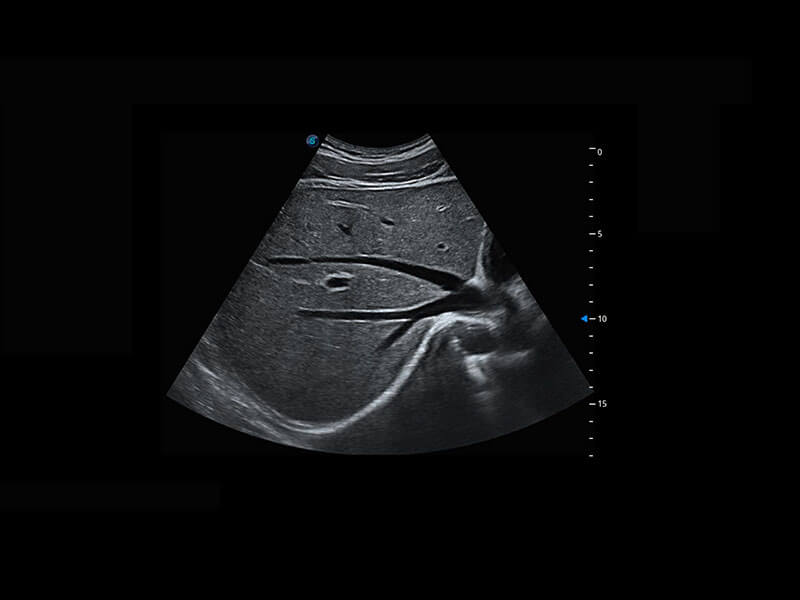

P60在胎儿早孕期超声筛查中为您带来优异的图像质量。

早孕-胎心